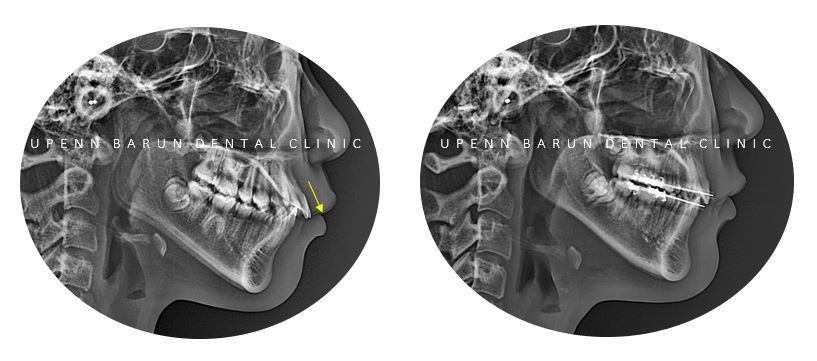

교정치료 전 사진, Initial Photo

정밀진단을 해보니

윗니와 아랫니 사이의

간격이 큰

수평피개 교합과

치아가 너무 깊게 물리는 과개교합

상태였습니다.

교정기간: 22/3~24/3